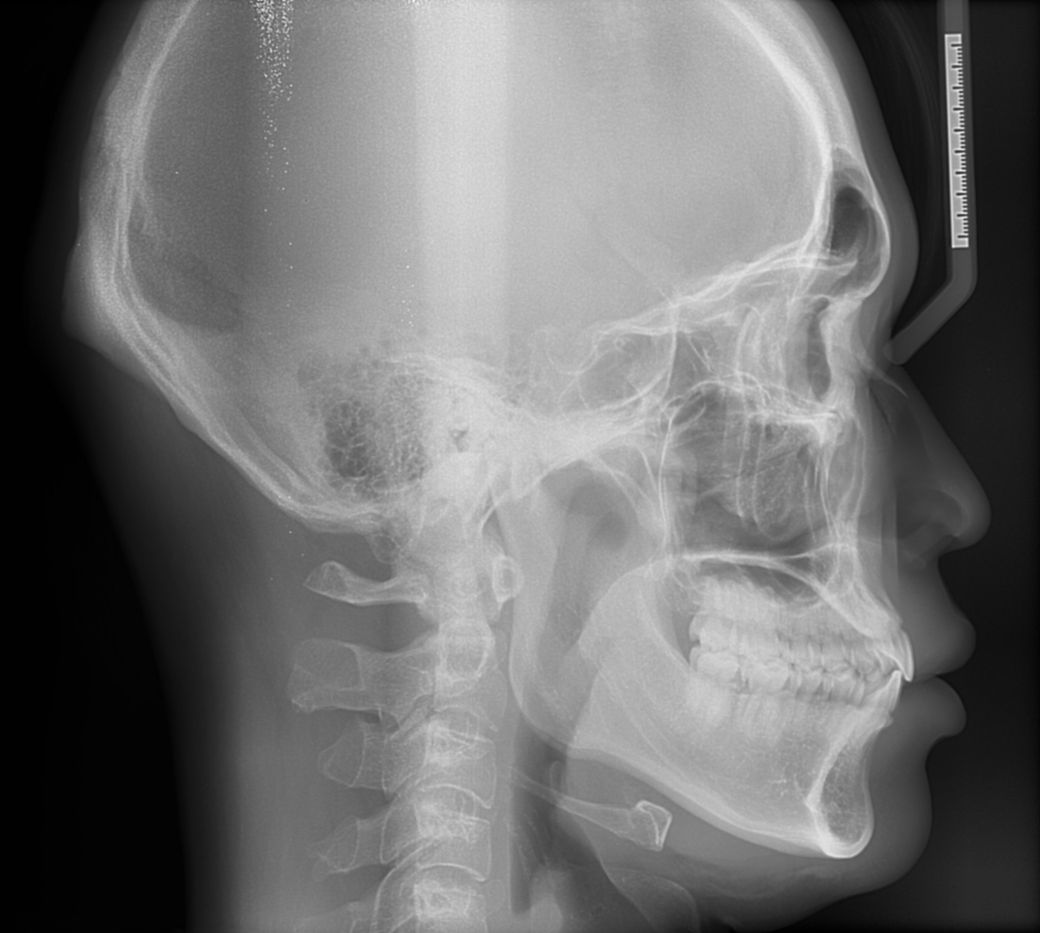

돌출입 교정 상담 받았는데 치과에서 앞니 치근이 짧다고 발치 교정은 추천하지 않으며 또한

비발치 전체 교정으로 사랑니 공간으로 치아전체 후방이동 또한 무리일 것 같다고 합니다

원하는 결과를 얻기에는 교정보다는 양악수술 쪽을 고려해 봐야 한다고 했습니다

교정 자체를 하는 것이 심미적인 목적이라면 지금 상태에서는 양악을 하는 것이 맞습니다. 치근단이 짧을 경우에는 치근 흡수 등이 일어나면 돌이킬 수 없는 결과로 이어질 수 있습니다. 다만 현재 안모 사진으로 보았을 때는 교정을 하지 않더라도 기능적인 부분은 전혀 문제가 없을 것으로 보입니다.

다만 질문자님이 본인의 안모가 마음에 안든다면 지금으로서는 대학병원 방문 후 양악을 하셔야 합니다.